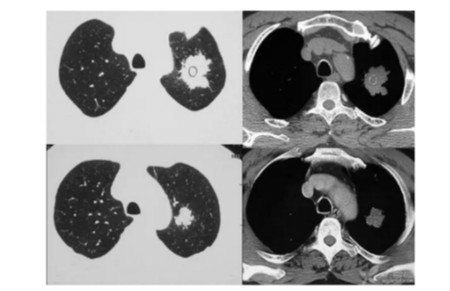

周围型肺癌又称肺野型,系指发生于肺段以下支气管直到细小支气管的肺癌。

临床症状出现较晚。周围型肺癌的基本征象主要有分叶征、毛刺征、空泡征、支气管充气征、胸凹陷征、血管集束征及空洞、钙化等。周围型肺癌的临床表现较晚一些,常有患者诊断时已是晚期阶段,从而耽误了最佳治疗时间,影响其治疗结果。